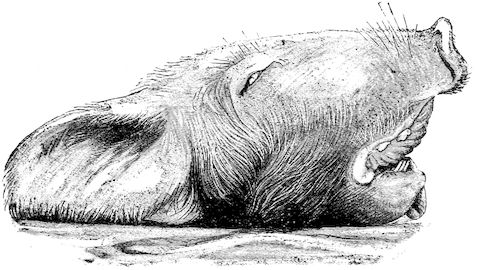

Fig. 3.—Pig suffering from osseous cachexia (fourth stage).

Such shocks would be of no importance to a healthy animal, but to one suffering from osseous cachexia, any violence, or even the slightest muscular effort may be followed by fracture of the gravest character, involving even the vertebral column. In cows the pelvis, femur, and tibia are most frequently injured.

In horses, particularly in riding horses, fractures are commonest in the region of the forearm, cannon bone, and anterior phalanges. So extremely fragile are the bones at this stage that the horse represented herewith broke twelve ribs at one time by simply falling on its side. It is interesting to note that such fractures are never accompanied by any extensive bleeding. They have little tendency to repair, no real callus formation occurs, and on post-mortem examination one often finds the ends unconnected by temporary callus, worn, and rounded by reciprocal friction.

At this stage but under other circumstances, the animals show great reluctance to rise, remaining down for twelve to twenty-four hours without shifting their position. If forced to get up, they stand as though fixed in one position, the respiration and circulation become rapid, and they soon grow tired and fall.

114. The fourth phase, or period of osteomalacia, i.e. softening of the bones, is also the last. It is rarely seen in large animals like horses and oxen, because accidents so often accompany the preceding stages and necessitate slaughter; but it is common in goats and pigs.

In this phase the bones become elastic, soft and depressible, yielding to the pressure of the operator’s fingers.

Fig. 4.—Deformity of the face in the horse shown in Fig. 2.

The flat bones are particularly liable to this change, which is common to domesticated animals. The bones of the head are the first to suffer; later those of the pelvis. The lower jaw becomes swollen, particularly about the centre of the branches which may attain three, four, or five times, their normal thickness.

The depression in the submaxillary space disappears. The upper jaw undergoes similar changes, becoming deformed and thickened until the cavities of the sinuses and the hollow appearance of the palate are lost, while the face is so changed that it cannot be recognised as that of a horse, goat, etc.

The molar teeth are almost buried, their tables alone being visible at the bottom of a depression, the edges of which rise above the neighbouring parts (pig).

Mastication is clearly impossible, the jaws appear paralysed, the muscles powerless, and only swallowing is possible, a fact which explains why life is only prolonged to this stage in animals which can be fed with a spoon or bottle (pigs and goats). The bones of the cranium, although greatly changed in texture, are always less deformed than those of the face.

The changes are such that it is often easy with a mere post-mortem knife to cut the head completely in two. Osseous tissue, properly so-called, has disappeared.

All the constituent tissues, with the exception of the skin and muscles, i.e., the bone, periosteum and aponeuroses, have the appearance and consistence on section of the fibro-lardaceous tissue seen in chronic inflammation.

Regarding the development of the disease in pigs, we may repeat what has just been said respecting the goat. Walking on the knees is often one of the first signs, fractures are somewhat rare, and the period of softening and deformity is always very noticeable.